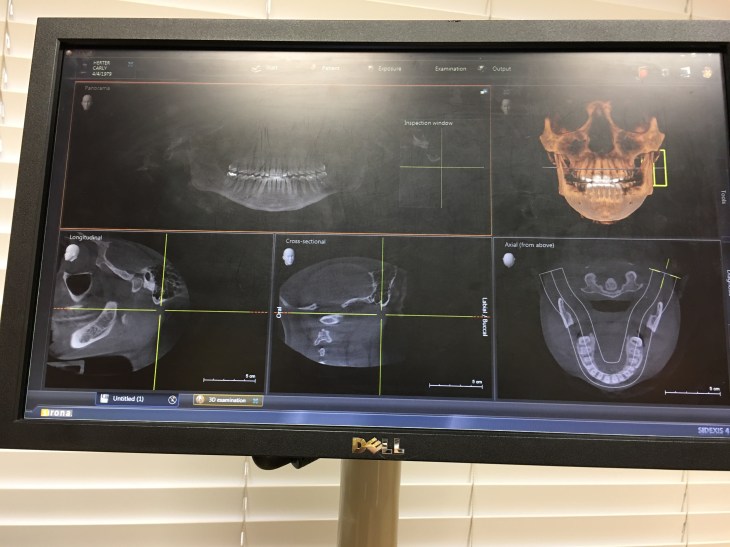

(Pictures from my CT scan the day before surgery. )

So, in other words, a cavity is a hole in the tooth and a cavitation is a hole in the bone.

How do you know you have a cavitation? My holistic dentist used a 3D cone beam scan and my Surgeon used a CT scan. The cavitation appears as a shadow on the scan and can be missed by doctors that are not familiar with them. Once scanned I made an appointment with my dentists suggested local holistic surgeon. I was not comfortable with him after meeting him and decided to look around. After much research I decided to go with Dr. Nunnally in Texas. This choice was based on long-term success rates, cost, and practice. Dr. Nunnally performs this surgery far better than any other doctor in my opinion. Many cavitation surgeries have a high recurrence rate because they aren’t closed and cleaned up properly and the immune system isn’t prepped appropriately. Dr. Nunnally uses Vit. C IV drips for three days, ozone, platelets and stem cells to fill in the surgical spaces. The recovery period has been amazing with very little pain and swelling! Although I’m only a week out from my surgery I’m extremely hopeful that this will provide immense healing to my body!